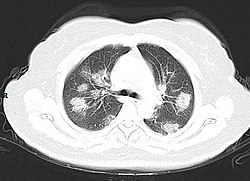

Imaging[edit | edit source]

Chest CT scans may be helpful to diagnose COVID-19 in individuals with a high clinical suspicion of infection but are not recommended for routine screening.[93][105] Bilateral multilobar ground-glass opacities with a peripheral, asymmetric, and posterior distribution are common in early infection.[93][106] Subpleural dominance, crazy paving (lobular septal thickening with variable alveolar filling), and consolidation may appear as the disease progresses.[93][107] Characteristic imaging features on chest radiographs and computed tomography (CT) of people who are symptomatic include asymmetric peripheral ground-glass opacities without pleural effusions.[108]

Many groups have created COVID-19 datasets that include imagery such as the Italian Radiological Society which has compiled an international online database of imaging findings for confirmed cases.[109] Due to overlap with other infections such as adenovirus, imaging without confirmation by rRT-PCR is of limited specificity in identifying COVID-19.[108] A large study in China compared chest CT results to PCR and demonstrated that though imaging is less specific for the infection, it is faster and more sensitive.[92]